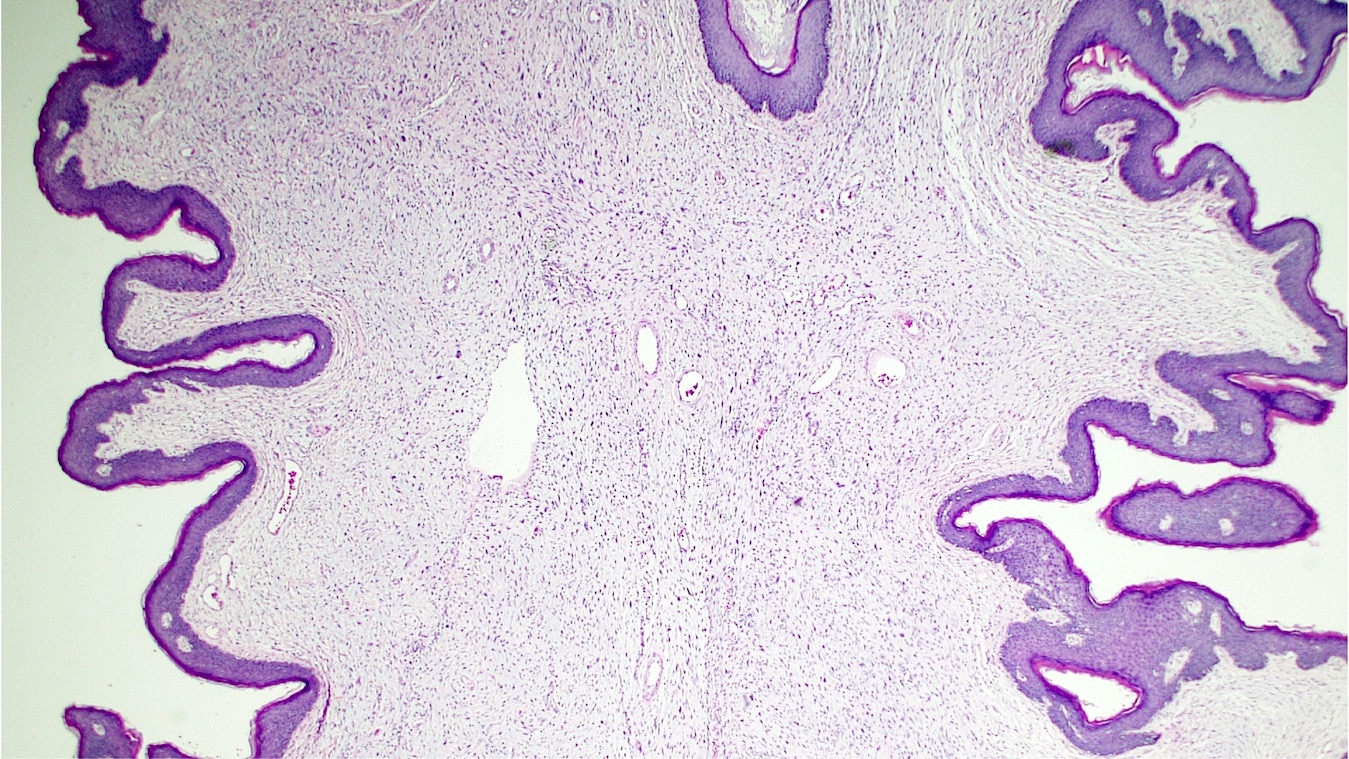

Microscopic (histologic) description

- Polypoid and noncircumscribed, extending to the epithelial / subepithelial interface (J Low Genit Tract Dis 2011;15:69, Am J Surg Pathol 2000;24:231)

- 2 stromal cellularity variants: hypocellular form (spindle cells set within a loose collagenous myxoid-like stroma) or hypercellular variant (exhibits marked nuclear pleomorphism and frequent mitoses, including atypical forms), especially during pregnancy, therefore mimicking leiomyosarcoma or rhabdomyosarcoma (Am J Surg Pathol 2000;24:231)

- Overlying squamous epithelium may display reactive changes but without papillomatous architecture or koilocytosis, which distinguishes it from condyloma acuminatum (caused by human papillomavirus) (Am J Surg Pathol 2005;29:460)

- Stellate cells should not be interpreted as sarcoma (J Low Genit Tract Dis 2011;15:134)

- Commonly found around blood vessels or near the epidermal stromal interface

Microscopic (histologic) images